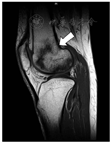

患者,女性,63岁,主因"反复腰腿疼痛14年"入院。患者于2006年因"特发性血小板减少性紫癜"使用大剂量激素治疗(强的松每日12片间断服用约1年的时间)后出现腰背部及腿部疼痛,逐渐加重至不能行走,就诊于华西医院内分泌代谢科后诊断为严重骨质疏松症,予以阿仑膦酸钠片、阿法骨化醇及钙尔奇D3治疗后疼痛症状缓解。6年前(2014年)无明显诱因出现双膝关节疼痛明显伴活动受限,完善CT及MRI(磁共振成像)提示膝关节上方股骨远端骨质破坏,髓腔内密度不均成地图样改变,多系骨梗死(图1)。收入内分泌代谢科后予以唑来膦酸(密固达)、普通维生素D3、钙尔奇D3和阿法骨化醇治疗后双膝关节疼痛逐渐缓解。此后患者分别于2015年9月24日、2016年10月14日、2017年12月13日、2019年2月28日及2020年5月30日,先后共6次输注唑来膦酸抗骨质疏松治疗。经治疗后患者双膝及腰背部疼痛明显缓解(VAS评分0分),双膝活动自如。2020年5月复查MRI提示:右股骨远端、右侧髌骨内见不规则地图样混杂信号影,与2014年比较,水肿影消失,病灶缩小且边界清楚(图2)。患者经过6年唑来膦酸治疗,双能X线吸收检测法(DXA)骨密度提示腰椎骨密度能够维持并较前有一定增长(图3),L1-4平均值增加2.5%,股骨颈及全髋分别降低约8.7%和7.8%。骨转换标志物也控制在较低水平(表1),从中也可以观察到唑来膦酸对于骨吸收的抑制作用远大于对骨形成的抑制。

注:MRI:磁共振成像